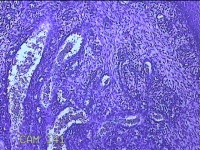

宫颈赘生物

性别

女

年龄

49岁

临床诊断

人乳头瘤病毒感染

一般病史

宫颈HPV阳性TCTLSLL

标本名称

大体所见

灰白粉红色肿物1.2x0.8x0.2cm两个,表面光滑。

图1